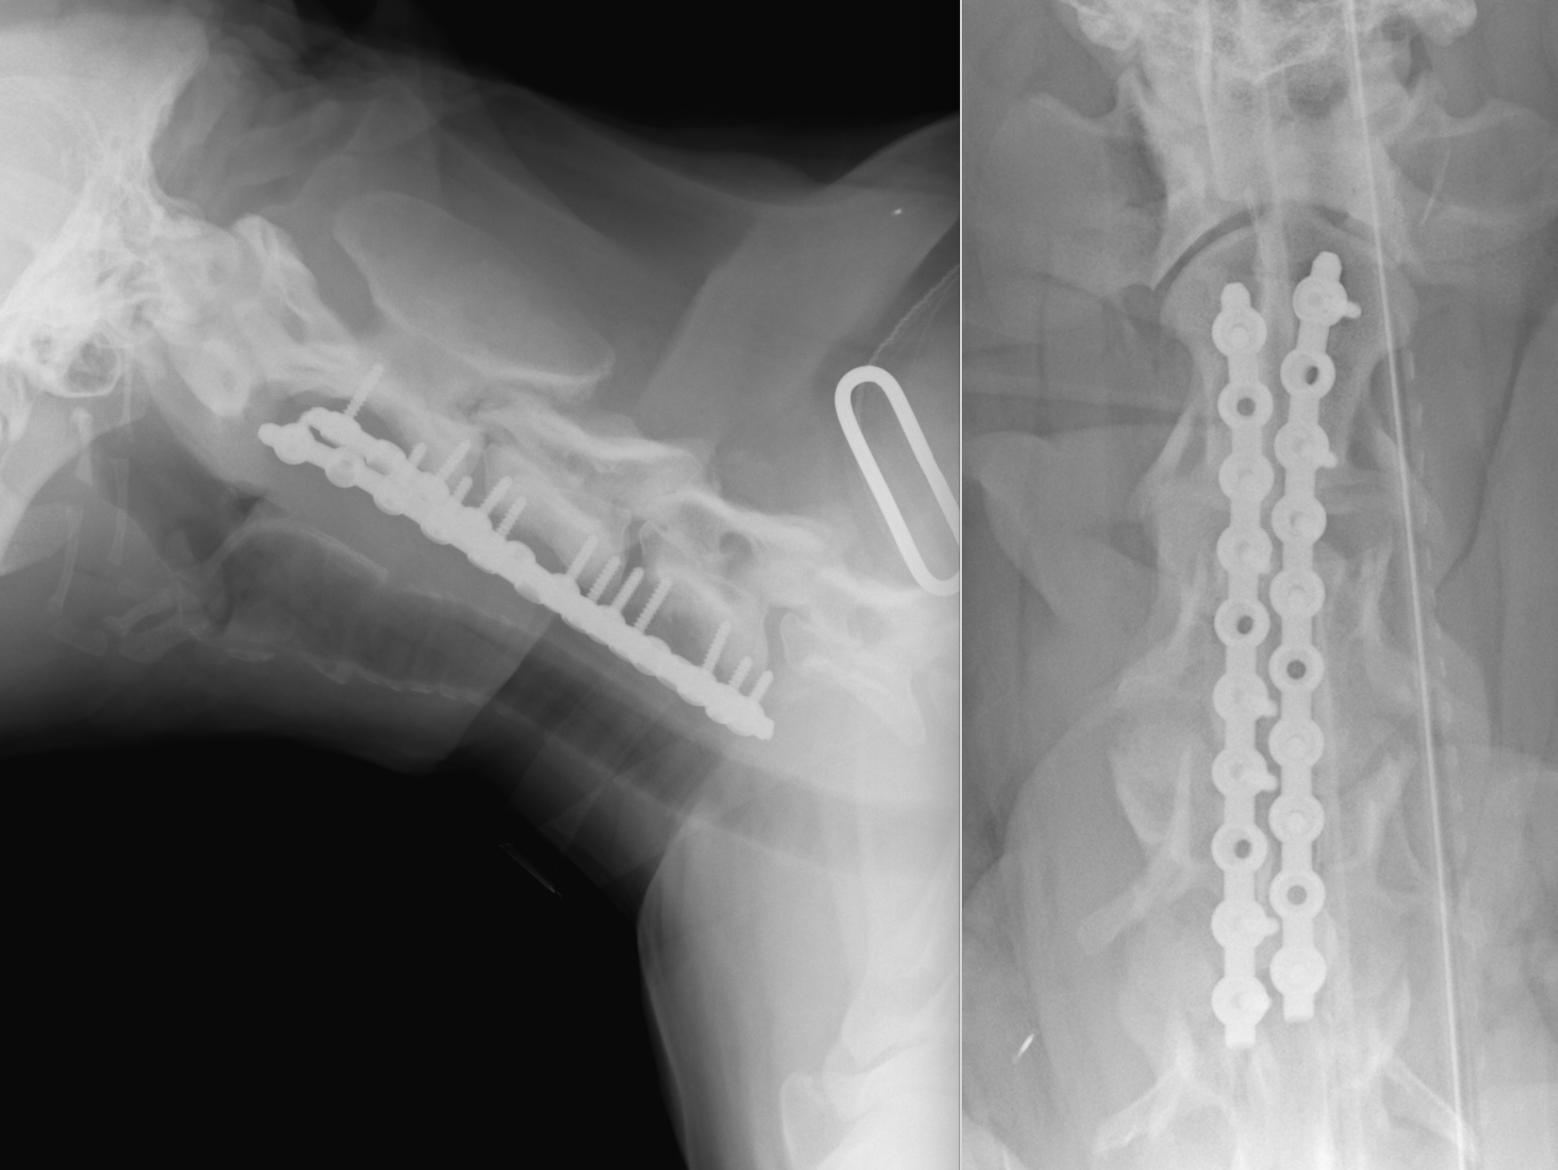

術前検査として単純X線画像検査、造影X線画像検査、MRI検査、CT画像検査を実施し、頚部2-3,3-4,5-6,6-7の部位に脊髄の狭窄が認められました。

X線CT画像検査です。特に頚椎2−3領域で左右からの重度の圧迫が確認されました。椎間板の問題ではなく、骨自体の形・形態異常からくるものと判断しました。

今回使用する予定のチタン製プレートSOPと呼ばれるものです。動物で使う最大のサイズ3.5mmです。術後にMRIが必要になったときのために、通常のステンレスではなく、チタンを用いています。

手術では計画を立てた位置で骨の切削を行い、減圧を実施し、同時に不安定性を解消するためにプレートによる固定を実施しました。骨の切削に4時間、固定に3時間かかり、すべてで8時間ほどの長時間の手術となりました。今回は責任病変が前方の2-3-4であろうと判断し、そこをメインに手術を実施しました。術後すぐの歩様動画です。術後はコルセットを装着しています。まだふらつきが残っている状態です。

術後のX線画像検査です。